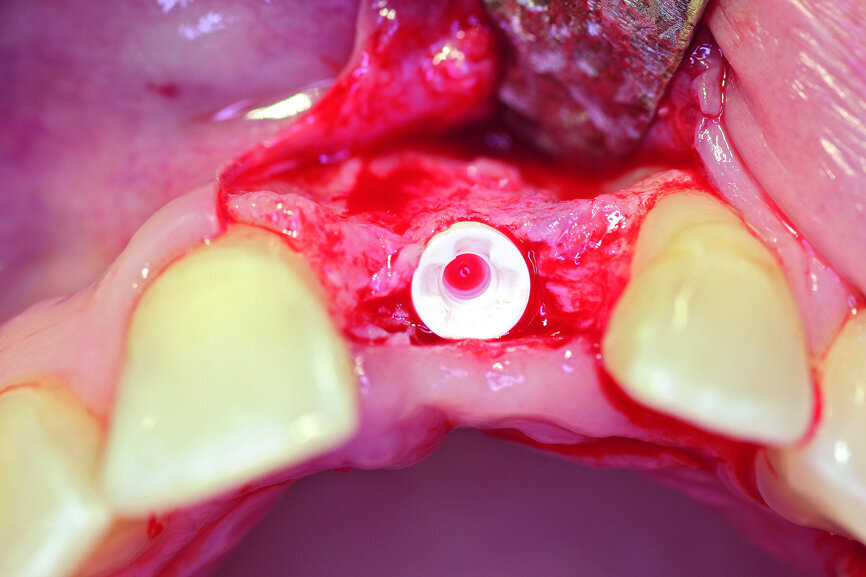

Fig. 5a: A two-piece ceramic implant was inserted.

Fig. 5b: A two-piece ceramic implant was inserted.

After extraction of tooth #21, the apical granulation tissue was excochleated through a semilunar incision (Fig. 3). A two-stage procedure was performed to prevent failure of osseointegration of the ceramic implant and to preserve the soft-tissue structures (papillae and attached gingiva). A claspless prosthesis made from Valplast (Valplast International) served as a temporary restoration. The implant site in region #21 was uncovered after five months (Fig. 4). A two-piece ceramic implant (diameter: 4.2 mm; length: 12.0 mm) was then inserted (Figs. 5a & b). The guidelines for implant placement in the aesthetic zone and the drilling procedure specified by the manufacturer were observed.13, 14 Both vertical and transverse insertion depth are decisive for prosthetic success. The implant can be placed between 1.6 mm and 0.6 mm supracrestally because of a special thermal etching procedure in the collar region; the insertion depth is determined by the gingival height and the existing bone of the adjacent teeth. The implant positioning should be approximately 2–3 mm subgingivally because the abutments are added 1 mm above implant shoulder level. Transversal bone augmentation was performed with a mixture of autogenous bone chips (retrieved from the retromolar mandible), xenograft (Geistlich Bio-Oss, Geistlich Biomaterials) and guided bone regeneration (Jason membrane, botiss biomaterials; Figs. 6a & b). The exposure was performed after four months using a PEEK gingiva former (Fig. 7).